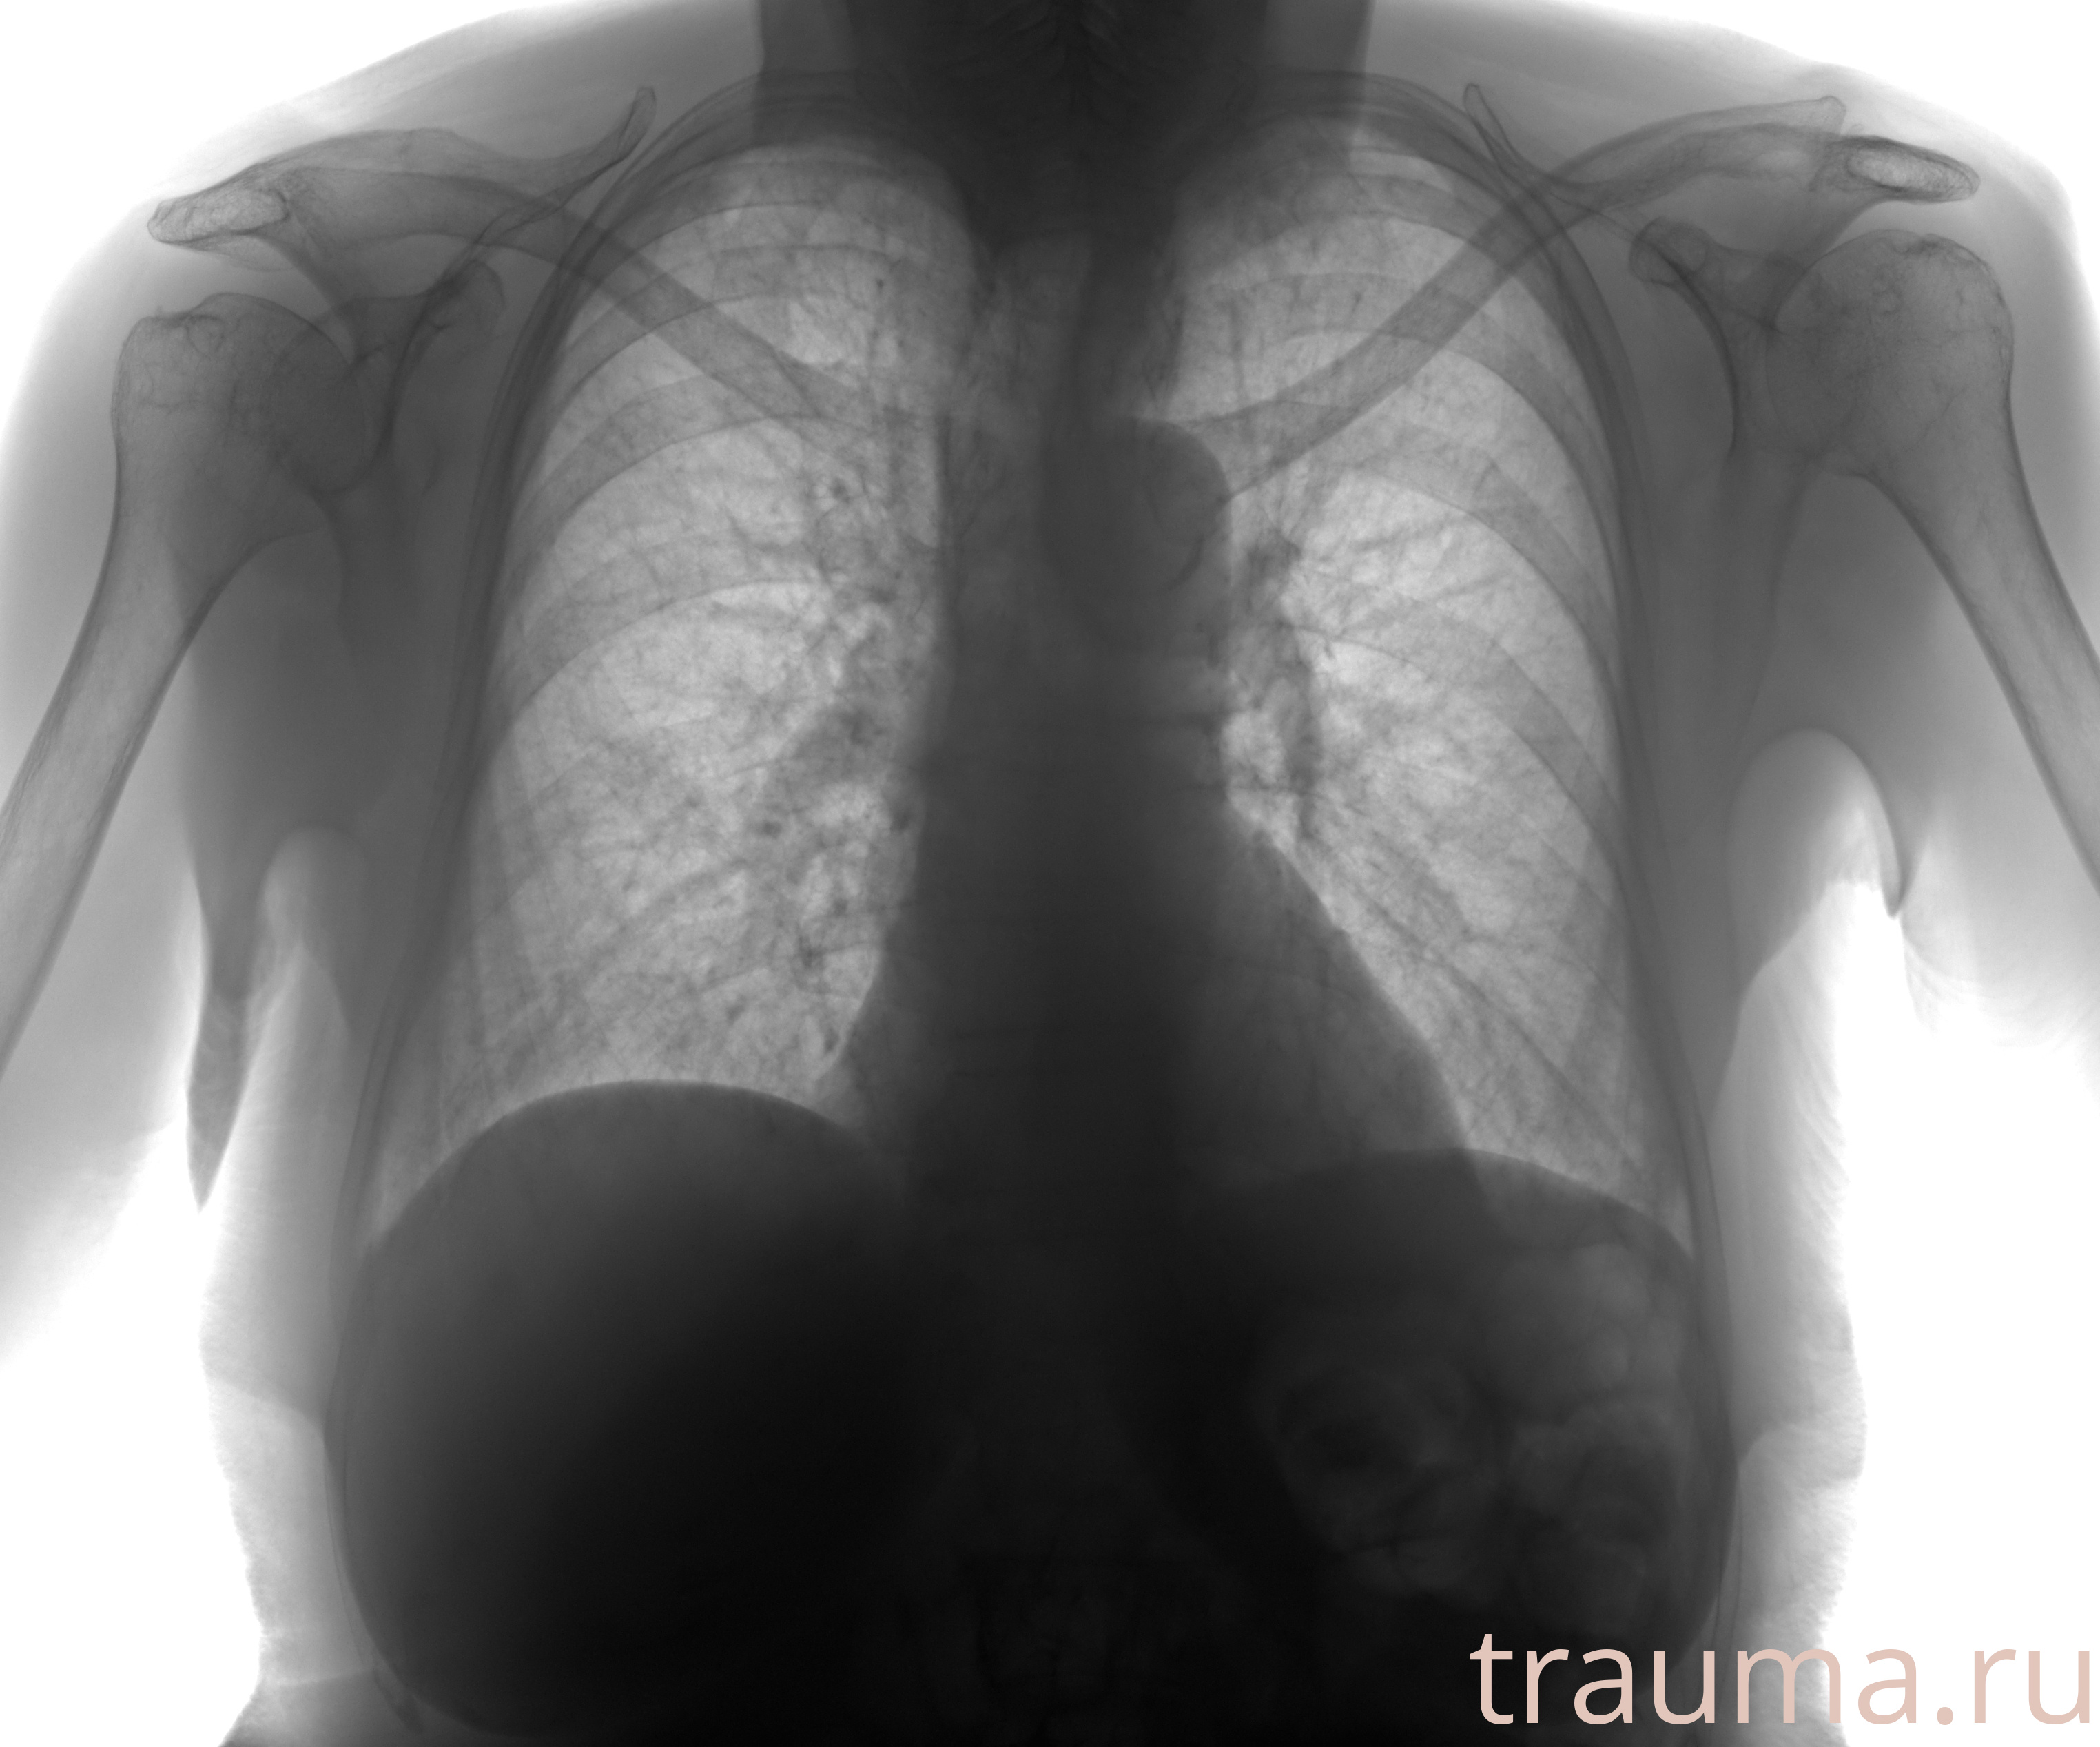

Рентгенограммы

Рентген на дому: по вашему адресу приезжает врач-рентгенолог, травматолог-ортопед с мобильным рентгеновским аппаратом, проводит диагностику травмы или заболевания, делает необходимые рентгенограммы, дает рекомендации по дальнейшему лечению. Получить качественные снимки в домашних условиях возможно благодаря уникальной методике, разработанной МосРентген Центром для института  Склифосовского